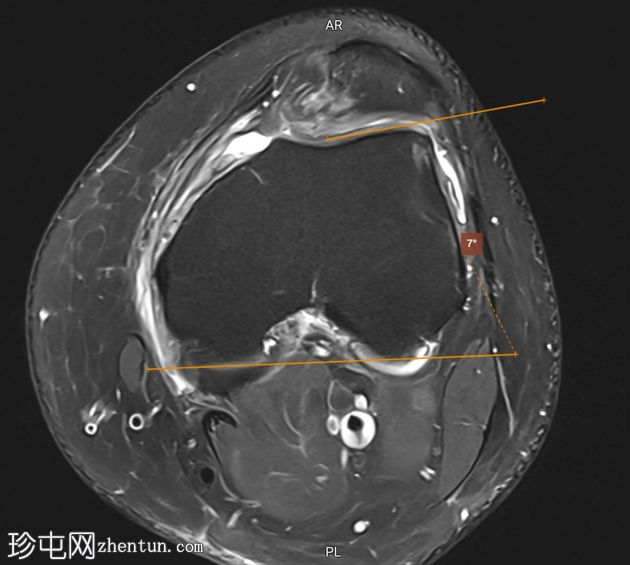

轴位PD序列

脂肪抑制序列

标注图像

5.png

滑车

深度

滑车沟

6.png

角度

滑车外侧

7.png

倾斜度

8.png

改良的

Insall-Salvati 比值

滑车深度 < 3 mm

滑车沟角度 > 150°

滑车外侧倾斜度 < 11°

影像学表现符合滑车发育不良

改良的 Insall-Salvati 比值 1.7(在正常范围内)